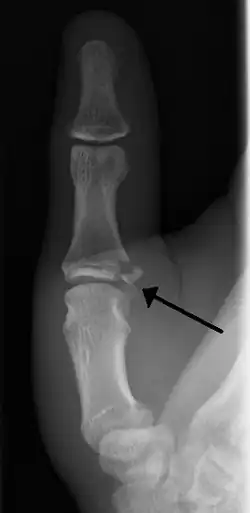

| Avulsion fractures of the ulnar base of the proximal phalanx of the thumb ( Gamekeeper's fracture ) | |

- Avulsion of distal UCL causing the pulling off of a bone chip off the proximal phalanx base.[3]

When approaching this type of injury, the physician must first determine whether there is an incomplete rupture (or sprain) of the UCL, or a complete rupture. If the UCL is completely disrupted, the physician must then determine whether there is interposition of the adductor aponeurosis (Stener lesion), or simply a complete rupture of the UCL with anatomic or near-anatomic position. Radiographs are helpful in determining the possible presence of an avulsion fracture of the proximal phalanx insertion site of the ulnar collateral ligament. Stress examination, or one done under fluoroscopic guidance, can help determine the integrity of the ligament.